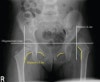

소아의 골반, 고관절, 대퇴골의 X-ray

- Pelvis AP view

- 3 Lines

- Acetabular angle

The acetabular angle using Hilgenreiner's line should be less than 28 degrees at birth.

The angle should become progressively shallower with age.

The normal range is 33 to 38 degrees.

Angles above 47 degrees are seen in patients with acetabular dysplasia.

A measurement between 39 and 46 degrees is indeterminate.